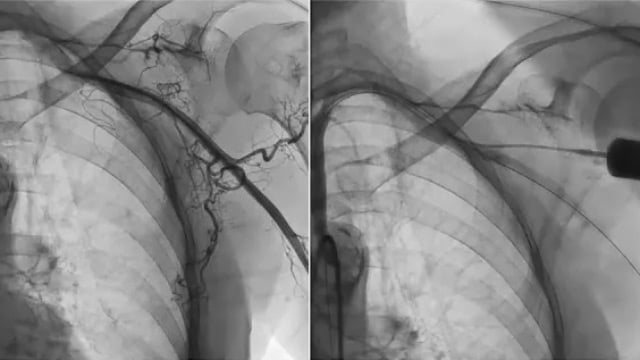

This session delivers expert insights into predicting and preventing coronary artery obstruction during TAVI procedures. Attendees will learn comprehensive assessment strategies for both native and bioprosthetic valves and explore advanced techniques to minimize occlusion risk in high-risk patients, including discussion of the UNICORN approach.